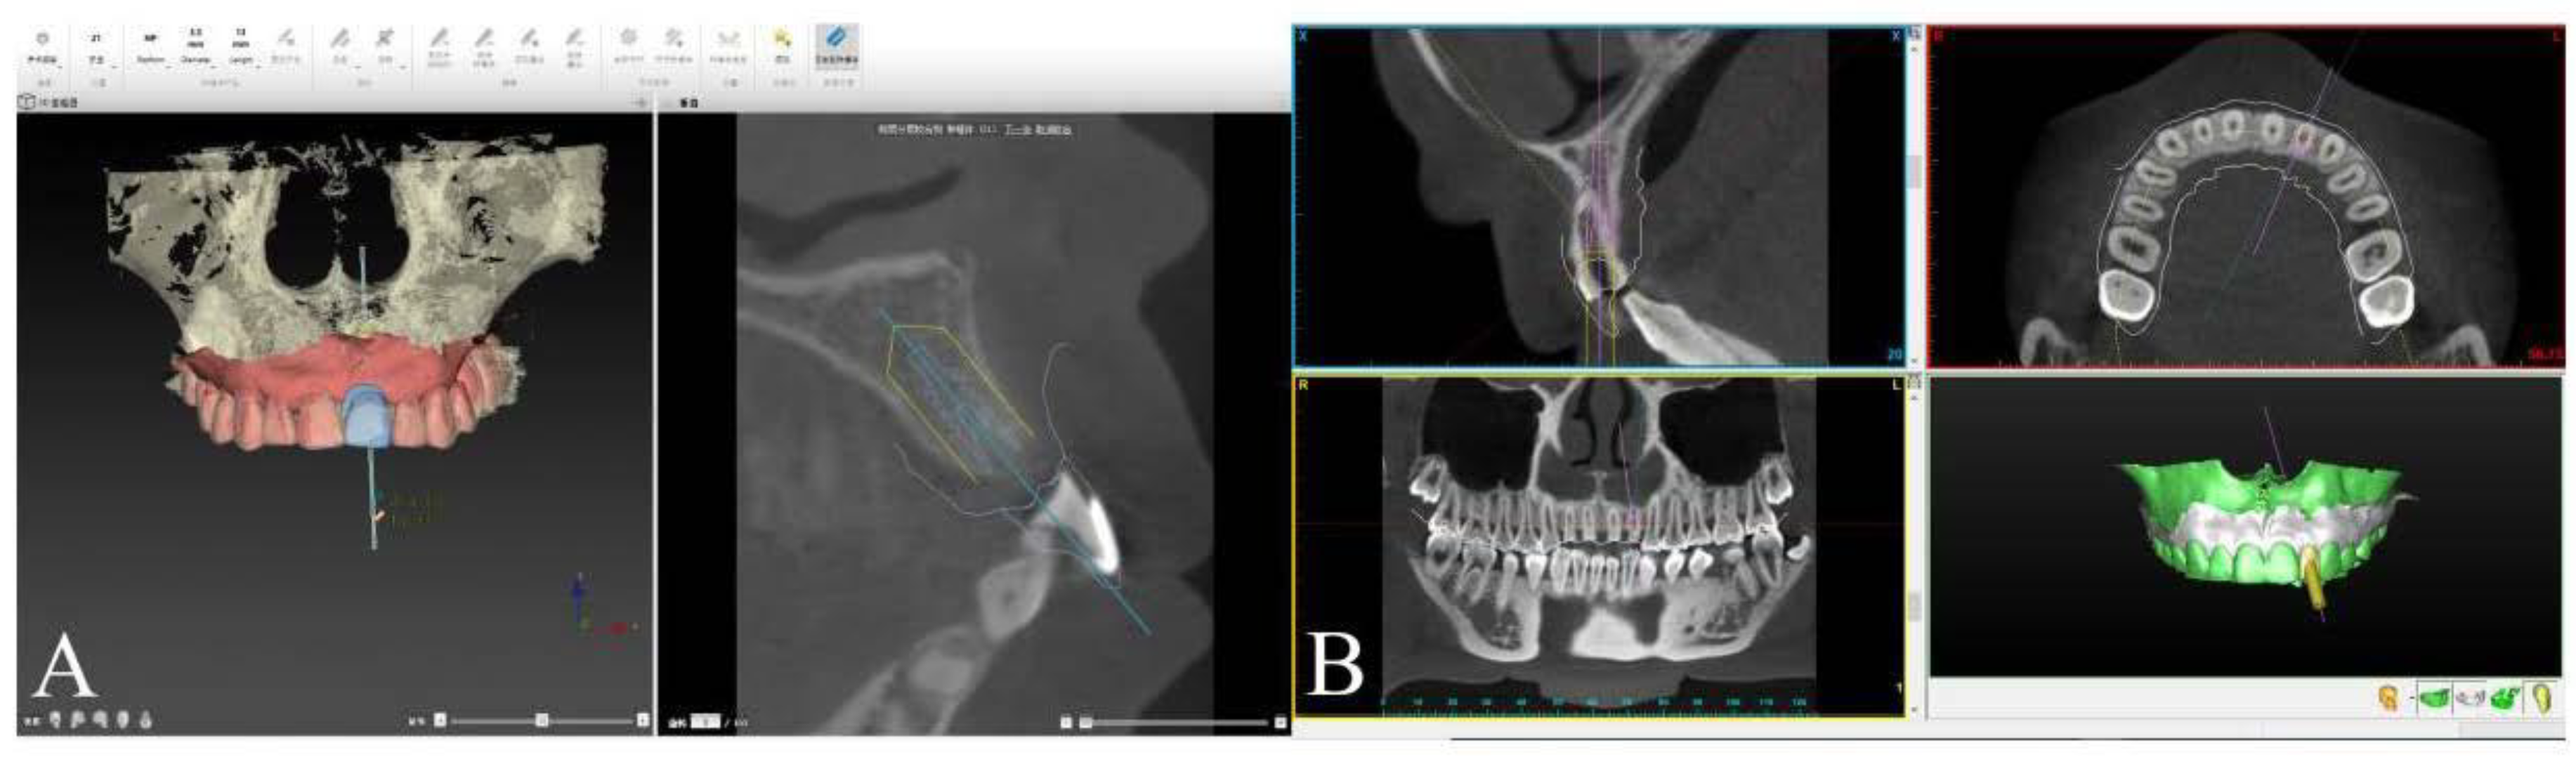

2.3. Implant Planning Procedure and Template Fabrication

2.4. Surgical Procedure